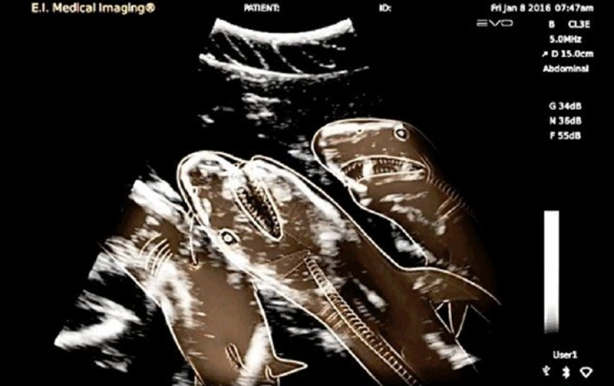

Hamile köpekbalığı

#18